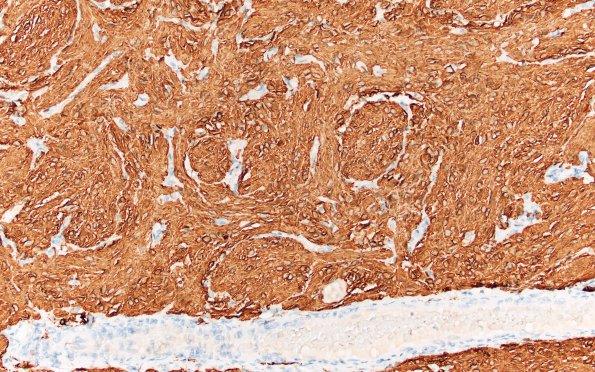

29C (Case 29) GFAP 20X

Piloid GFAP-immunoreactive tumor cells and unstained proliferated vessel (GFAP IHC)